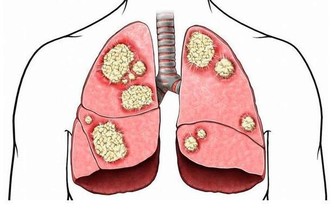

從醫學上來看,肺炎是一種肺部感染,它會導致肺泡出現膿液,使患者出現嚴重的呼吸困難或呼吸衰竭,進而引起死亡。肺炎屬於下呼吸道感染類疾病,根據世界衛生組織統計表明,這類疾病在每年導致全球約有200-300萬人死亡,位列人類死亡原因前五位。

我們都知道,武漢肺炎疫情出現的根源在於新型冠狀病毒感染,但造成肺炎的原因還有很多,醫學上可分為細菌性肺炎(常見於鏈球菌、肺炎支原體、流感嗜血桿菌、嗜肺性軍團菌等)、病毒性肺炎(常見如普通流感、呼吸道合胞病毒、鼻病毒等)、真菌性肺炎(常見於卡式肺、隱球菌物種、組織胞漿菌病物種等)。